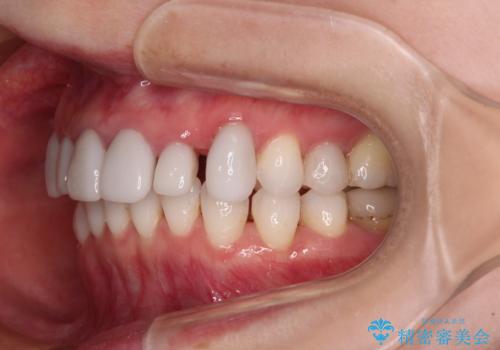

- 全体的なデコボコと、奥歯の欠損を放置した結果倒れ込んだ奥歯などを気にして来院された患者様です。

ワイヤー矯正の方が理想的な仕上がりとできる状態でしたが、上顎前歯にクラウンが装着されているため、インビザラインにて矯正治療を行うこととしました。

インビザラインのみで対応できないときにはワイヤー矯正を併用することとし、矯正治療後にはオールセラミッククラウンによる補綴治療を行うこととしました。

矯正治療自体はインビザラインで満足のいく仕上がりとなりました。

前歯は根管治療が必要となり、元々舌側に入り込んでいた左上2番目の歯は歯周外科処置により歯肉ラインを整えることとしました。

欠損部位は傾斜歯軸を起き上がらせることができたため、オールセラミッククブリッジにて補綴治療を行いました。

全顎的に満足のいく仕上がりとなりました。